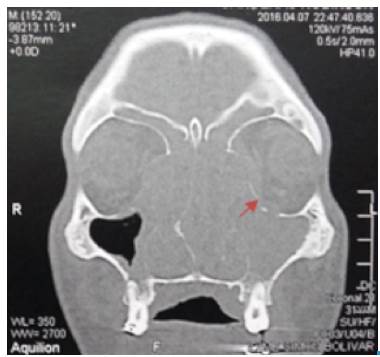

Blood tests were negative for human immunodeficiency virus (HIV), venereal disease research laboratory (VDRL) and hepatitis B and C, and C-reactive protein test (CRP) was less than 10 mg/L. Computed tomography scan in face and neck showed a mass occupying the nasal cavity, extended to the nasopharynx. The paranasal sinuses were occupied by homogeneous soft tissue density material; left lamina papyracea was eroded and the periorbital fat had inflammatory changes (Figure 2). Lymph nodes of the neck were compromised at zones IIa y IIb. The upper airway was patent. No lesions were identified in CT scans of thorax and abdomen. The patient was hospitalized and multiple punch biopsies of the soft palate were taken.